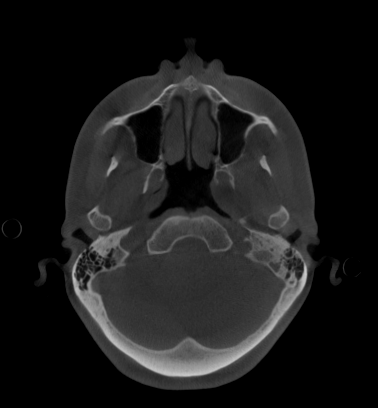

Imagen 3: Vista axial o transversal de CBCT de cráneo completo para cirugía ortognática (FOV 23×26). Imagen aportada por RD3D.

El CBCT 3D permite obtener una imagen tridimensional completa del esqueleto facial, ofreciendo información milimétrica sobre la posición de huesos, dientes y articulaciones.

- Reconstrucciones 3D realistas del cráneo y la mandíbula.

- Evaluación de asimetrías faciales y relación entre maxilares.